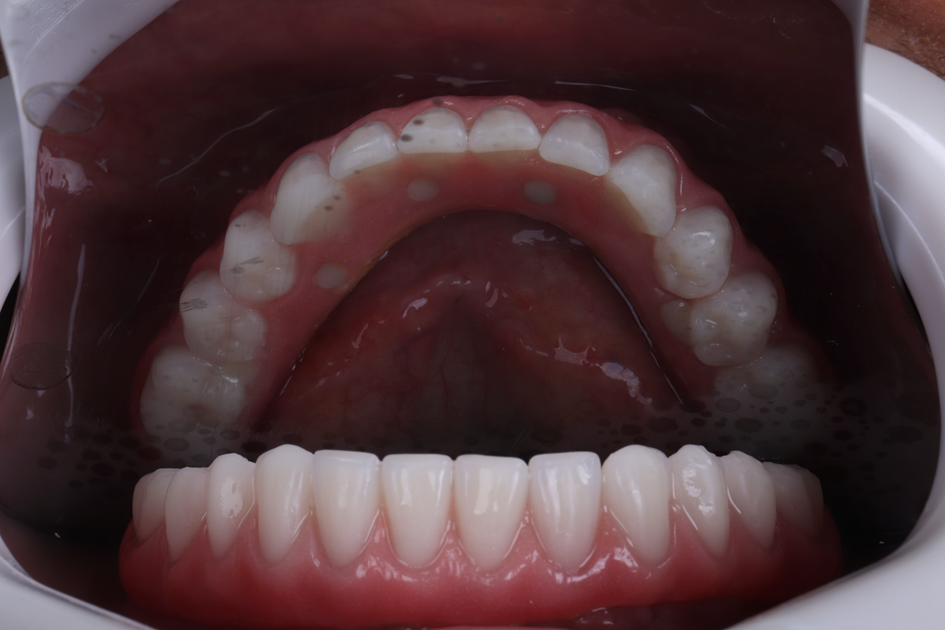

Figura 25 – Foto da prótese protocolo inferior definitiva.

Optou-se por confeccionar a prótese em um intervalo de quatro dias, respeitando etapas essenciais para garantir adaptação e estética adequadas. Foi realizada a prova dos dentes em cera, seguida da prova dos dentes montados sobre a barra metálica, e, por fim, a instalação da prótese definitiva.